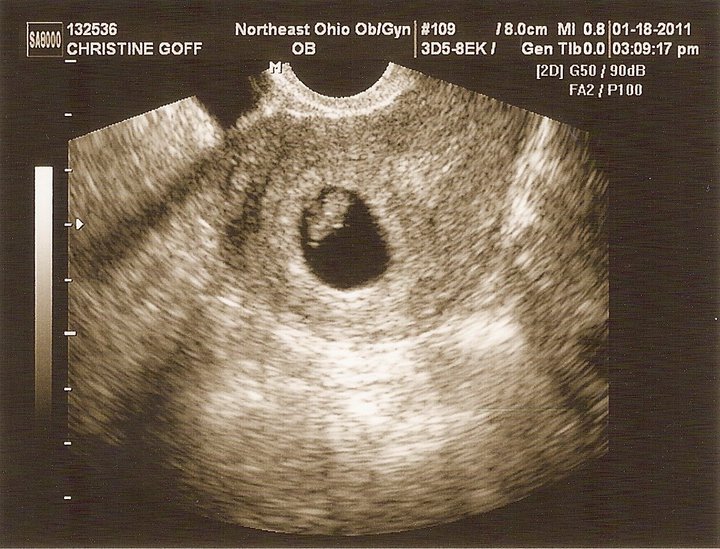

Ta-Da! I’m the father of a beautiful little….blob. That’s okay though, since it’s only 7 weeks old. According to BabyCenter.com, the baby is the size of a blueberry. Every time I think of that, I’m reminded of the old Willy Wonka movie: “I’ve got a blueberry for a daughter…”

Baby and Mom are doing very well, and everything is right on track. Heartbeat is very strong and steady.